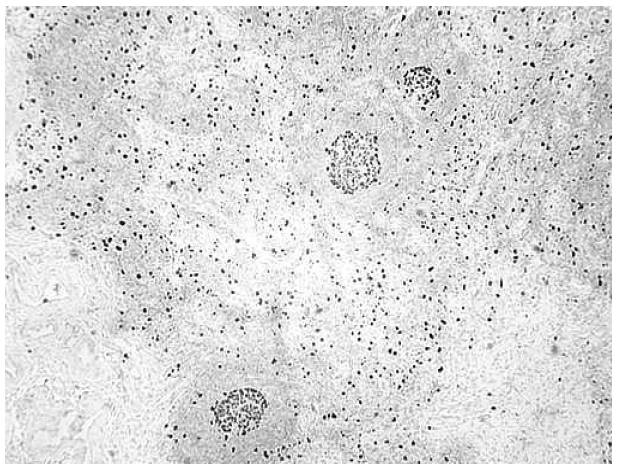

Лимфоидная ткань ПЛУ была представлена корковым веществом, содержащим первичные и вторичные фолликулы разных размеров, и мозговым веществом. Вторичные фолликулы характеризовались малыми размерами и неправильной формой. Однако у пациентов 2-й группы определялись и крупные фолликулы с хорошо выраженными центрами размножения (ЦР) и широкой мантийной зоной, состоящей из 6–10 слоев равномерно расположенных лимфоцитов. ЦР фолликулов были представлены стромальными клетками, макрофагами, единичными центробластами, малыми и средними лимфоцитами. Иммунобласты и митотически делящиеся клетки практически не встречались. Большая часть клеток в ЦР экспрессировала Ki-67-белок (рис. 2).

Рис. 2. Ki-67-положительные клетки в центрах размножения фолликулов и в корковом веществе. ИГХ: Ki-67. Ув. 10×4

У больных 1-й группы вторичные фолликулы выявлялись значительно реже по сравнению со 2-й группой. Многие фолликулы у пациентов 1-й группы не имели четких границ или отсутствовали.

Клеточный состав коркового вещества в тех участках, где в меньшей степени выражен склероз, был представлен лимфоцитами, в основном малыми и средними. Достаточно часто встречались большие лимфоциты, а иммунобласты выявлялись редко. Плазмобласты и плазмоциты определялись в основном в межфолликулярной зоне, где они формировали небольшие скопления, в то время как в мозговом веществе они практически полностью отсутствовали. В корковом и мозговом веществе равномерно располагались Кi-67-положительные клетки. При подсчете процентного соотношения Кi-67-положительных клеток среди клеток коркового вещества ПЛУ установлено, что их число во 2-й группе больных преобладало над их количеством в 1-й группе (21,6 и 12,3 % соответственно, р < 0,001). Среди Кi-67-положительных клеток во 2-й группе количество клеток с выраженной и умеренной экспрессией также было выше, чем их количество у больных 1-й группы. Такая же динамика относительного количества пролиферирующих клеток была характерна и для мозгового вещества: в 1-й группе Ki-67-положительные клетки составляли 11,8 %, во второй – 21,2 % (p < 0,001).

Увеличение количества Ki-67-положительных клеток у больных 2-й группы, наличие в корковом веществе ПЛУ вторичных фолликулов с активно пролиферирующими клетками свидетельствует об иммунной активации лимфоидной ткани. Активация иммунитета в ранние стадии ВИЧ-инфекции происходит в результате стимуляции лимфоцитов вирусом иммунодефицита и его антигенами, а также в связи с поступлением бактериальных продуктов из кишечника через разрушенный кишечный барьер [11]. При развитии хронической фазы инфекции опустошение лимфоидной ткани кишечника ведет к увеличению в крови больных концентрации бактериальных продуктов, что сопровождается стимуляцией макрофагов и дендритных клеток, ростом концентрации провоспалительных цитокинов (ИЛ-1, ИЛ-6, ИЛ-8, интерферонов) и сывороточных маркеров воспаления в крови, что, в свою очередь, является причиной активации иммунокомпетентных клеток. Развитие системного воспаления при ВИЧ-инфекции поддерживает высокий уровень пролиферации лимфоцитов в лимфоузле, несмотря на проводимую АРТ, что подтверждается более высоким содержанием Ki-67-положительных клеток во всех зонах ПЛУ у больных 2-й группы. Увеличение числа клеток с положительной экспрессии Ki-67-белка у больных 2-й группы свидетельствует об укорочении времени полужизни лимфоцитов и увеличении скорости их обновления. Однако отсутствие иммунобластов в фолликулах и клеток плазмоцитарного ряда в мозговом веществе говорит о нарушении процессов дальнейшей дифференцировки лимфоцитов. Изучение пролиферации Т-лимфоцитов на фоне эффективного подавления вирусной нагрузки при АРТ показало, что она снижается по сравнению с уровнем до лечения, но полного восстановления иммунной системы у больных не происходит [13].